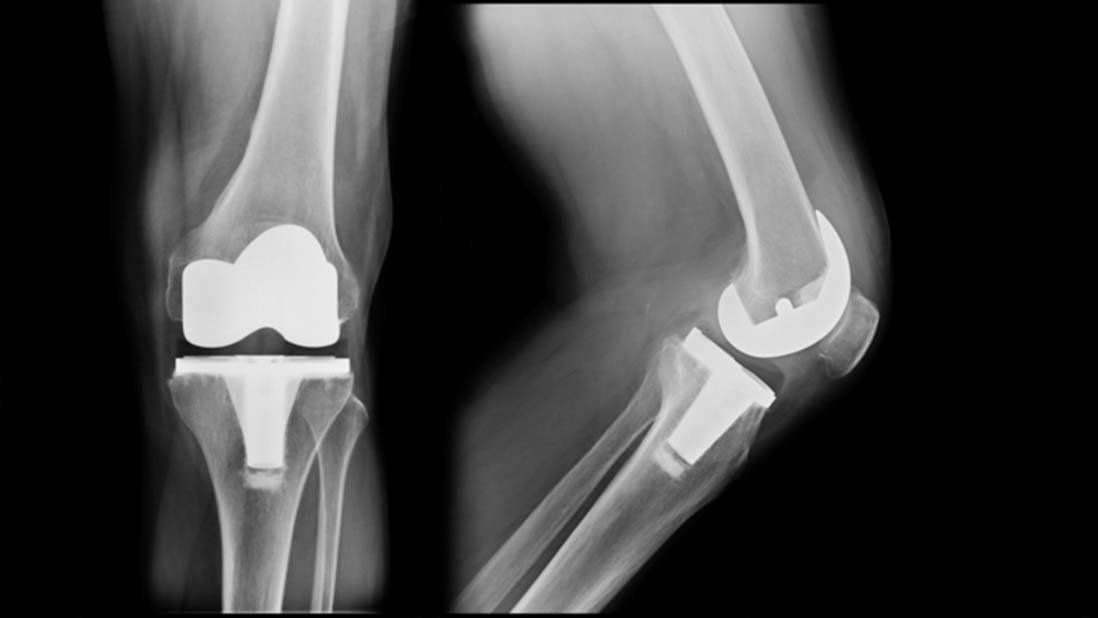

Total Knee Replacement is a surgical procedure in which the worn out or damaged surfaces of

the knee joint is removed and replaced with artificial components. This allows the knee to be

pain free and move smoothly aiming to establish healthy knee function similar to your native

knee & provide you with a superior quality of life.